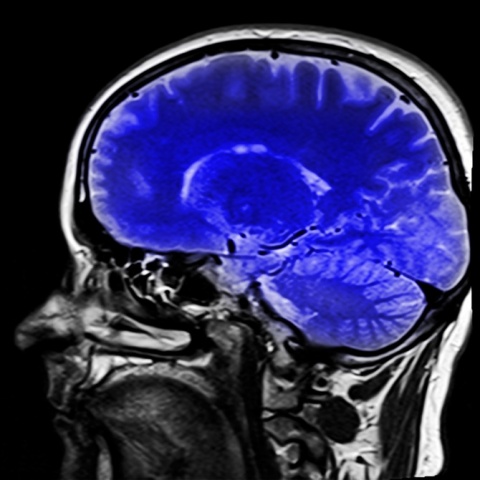

La cuestión de cuánto tiempo nos queda de vida es una incógnita que ha intrigado a la humanidad durante siglos. Si bien no podemos predecir con precisión la fecha de nuestro último aliento, la ciencia ha avanzado considerablemente en el campo de la longevidad y las expectativas de vida. Exploremos la posibilidad de calcular cuánto nos queda de vida, los factores que influyen en nuestra longevidad y cómo la ciencia se acerca cada vez más a responder a esta pregunta.

La longevidad, o la duración de la vida de un individuo, es un tema de gran interés en la ciencia y la medicina. A lo largo de la historia, la expectativa de vida ha aumentado significativamente gracias a avances en la atención médica, la nutrición y la higiene. Actualmente, la expectativa de vida promedio en muchos países supera los 70 años.